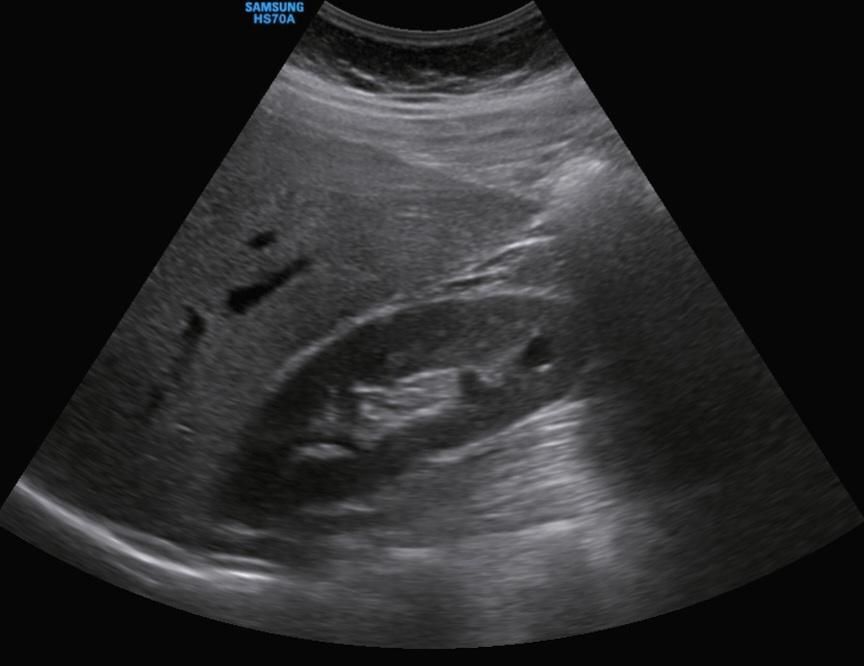

복부초음파 신장 낭종 어떤지 봐주세요

1. 단순 신장 물혹 같나요? 보스니악 1단계

1. 크기가 동그란 모양 아니어도 단순 물혹인가요?

2. 사진확대하면 가운데 안에 미세하게 하얀색 선 있는데 괜찮은건가요??

• 1번 째 사진

보여주신 초음파 이미지만으로 판단할 때는 전형적인 단순 신장 낭종(bosniak 1 가능성이 높아 보임) 쪽에 가깝습니다. 이유를 간단히 정리하면:

1. 경계가 비교적 매끄럽고 내부가 균일하게 어둡게(무에코) 보임

복잡낭종(보스니악 2 이상)에서는 내부 격막, 결절, 벽 비후 등이 보이는 경우가 많은데 그런 특징은 뚜렷하지 않습니다.

2. 모양이 완전한 원형이 아니어도 단순 낭종 가능

초음파에서는 장기·각도·압박에 따라 낭종이 약간 길쭉하게 보일 수 있습니다. 원형이 아니라고 해서 문제되는 것은 아닙니다.

3. 안쪽의 미세한 하얀 선

초음파에서 흔히 보이는 ‘경계면 반사(artifact)’로 보이며, 실제 격막이나 종괴로 보일 만큼 뚜렷하거나 두껍지 않아 위험 소견으로 보이진 않습니다.